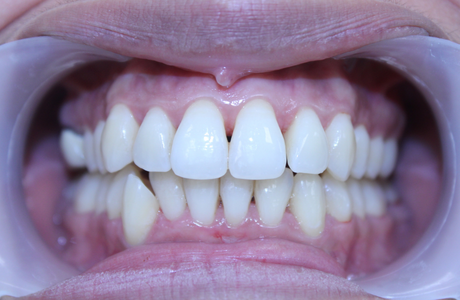

La gingivite est le premier stade de la maladie parodontale. La jonction gencive-dent est colonisée par des bactéries qui déclenchent une inflammation de la gencive. Rouge, gonflée et douloureuse, la gencive se décolle de la dent et le tartre s’accumule sous la gencive. A un stade avancé et en l’absence de traitement, la gingivite évolue en parodontite.

LA PARODONTITE

Au stade de la parodontite, la destruction porte alors sur l’os de la mâchoire et les ligaments de soutien qui ancrent les dents (ligament alvéolo dentaire). Des poches parodontales se forment et les bactéries s’y accumulent, avec plus ou moins de pus. A terme, le déchaussement de la dent peut amener la perte de celle-ci, accompagnée parfois d’une collection purulente très douloureuse.